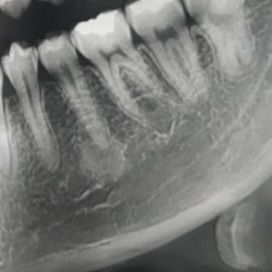

뿌리 염증이 보인다는데 엑스레이좀 봐주실수 있을까요?

작은어금니 끝에 염증이 약간 보여서 신경치료를 예약해놓은 상태입니다.

그런데 특별히 충치가 보이지는 않는대요 그래서 딱히 이유는 모르겠다는데,

신경치료 말고 따로 관리하거나 염증을 줄일수는 없는걸까요? ㅠㅠ

엑스레이 상에 보이는건 염증보다는 골 경화증일가능성이 있어 보이는데요. 증상이 없다면 그냥 두셔도 크게 상관은 없는거 같습니다.